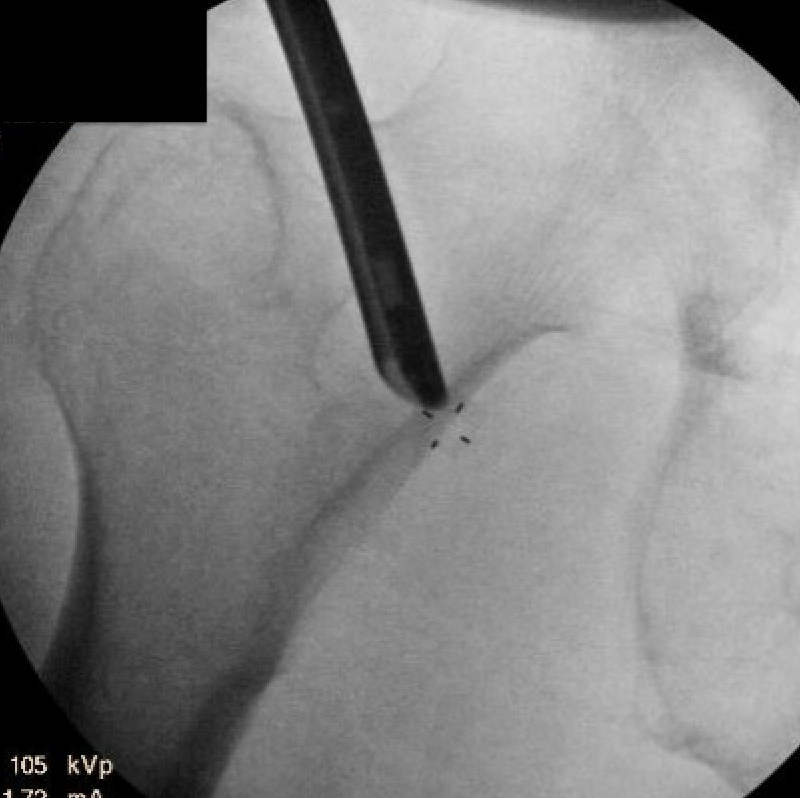

Injections

CT / Ultrasound guided local anesthetic and cortisone around quadratus

- diagnostic

- +-/ therapeutic